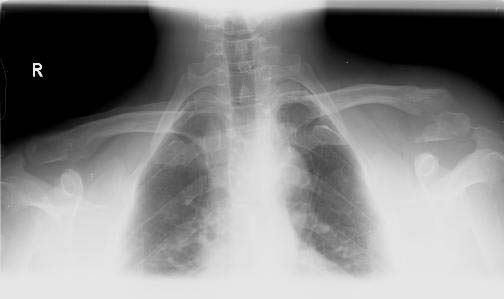

A 44 year old male 220 lb, but lean, body builder was riding his bicycle at about 30 km/hr and fell off onto his left shoulder. He is right hand dominant. He has an abrasion 3 cm posterior to the acromioclavicular joint. His left shoulder is anterior and caudad relative to the right shoulder. He is neurovasculary intact.

Radiographs show a displaced lateral 1/3 clavicle fracture (Neer type II). There is an inferior butterfly fragment that the conoid and trapizoid ligament most likely attach to.